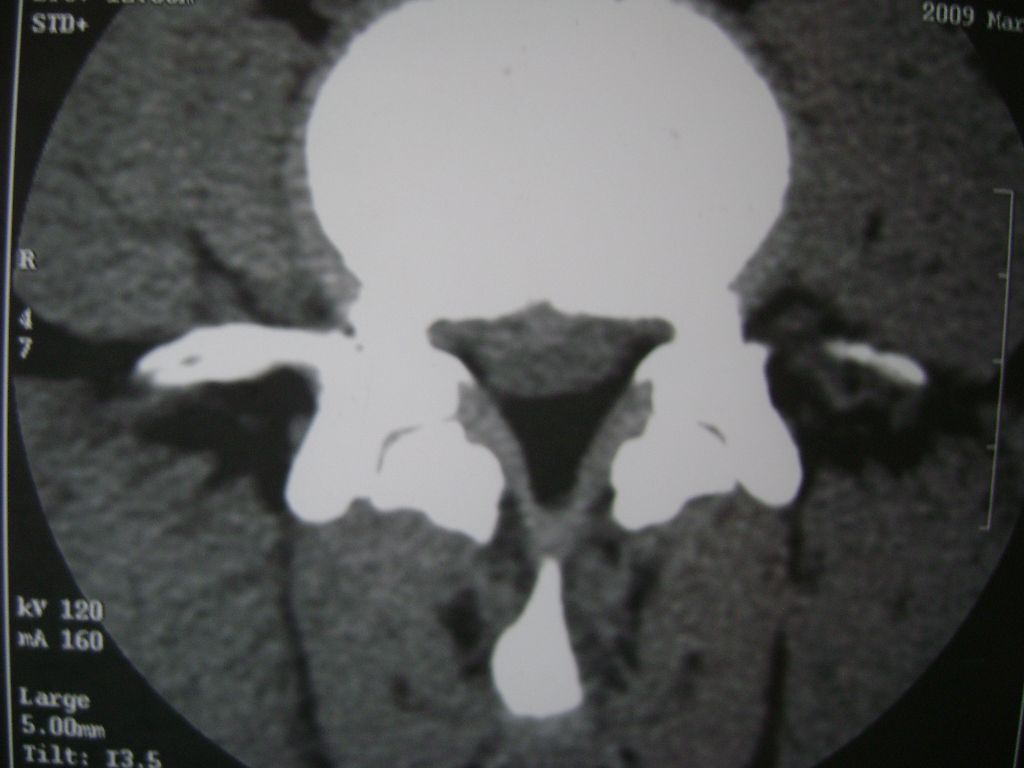

m  50  腰痛

两个椎盘均有膨出及突出改变,下一个尚有椎盘积气,后纵韧带钙化,另椎管脂肪过多症

椎间盘膨出,后纵韧带钙化,骨质增生

两个椎间盘中央型重度突出,黄韧带增厚。

两个椎间盘膨出并突出,下一个椎间盘变性;双侧黄韧带钙化。